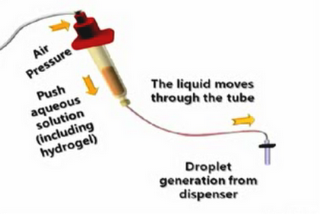

3D Tissue Printer Video

We bumped into a rather interesting video explaining and actually showing the process of using a 3D printer to deposit live cells! The video explains the main issue with tissue deposition: lack of a scaffold causes the deposited cells to lack structural integrity; they flop all over. The 3D printer enables them to… Continue reading 3D Tissue Printer Video

3D-Bioplotter

envisionTEC produces a rather unique device called the “3D-Bioplotter”. No, it does not print small mammals. Instead, it produces scaffolds. What are scaffolds? Tissue engineering often requires a “scaffold” on which to grow living tissue, otherwise, we assume, you’d end up with misshapen blobs of living goo. The scaffolds represent the desired final shape… Continue reading 3D-Bioplotter